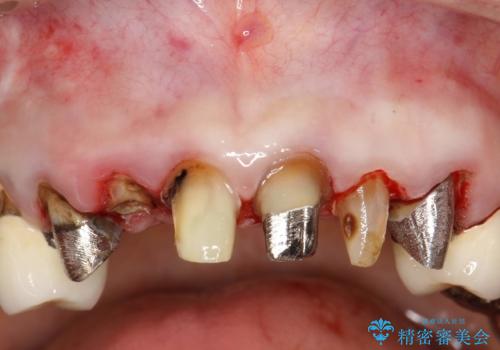

![[深い虫歯] 根管治療・歯周外科治療を行い歯を保存するの症例 治療前](https://seimitsushinbi.jp/wp/wp-content/uploads/2019/10/565cd81632432c46200480d3f4728f8d-500x350.jpg?v=1572444569)